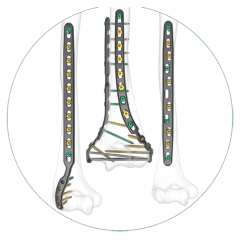

Explore our broad range ofOrthopedic Products

We are dedicated to improving the quality of life of patients suffering with bone and joint problems by delivering the latest medical devices that are proven to be effective and backed by scientific studies and research

• Surgical Devices